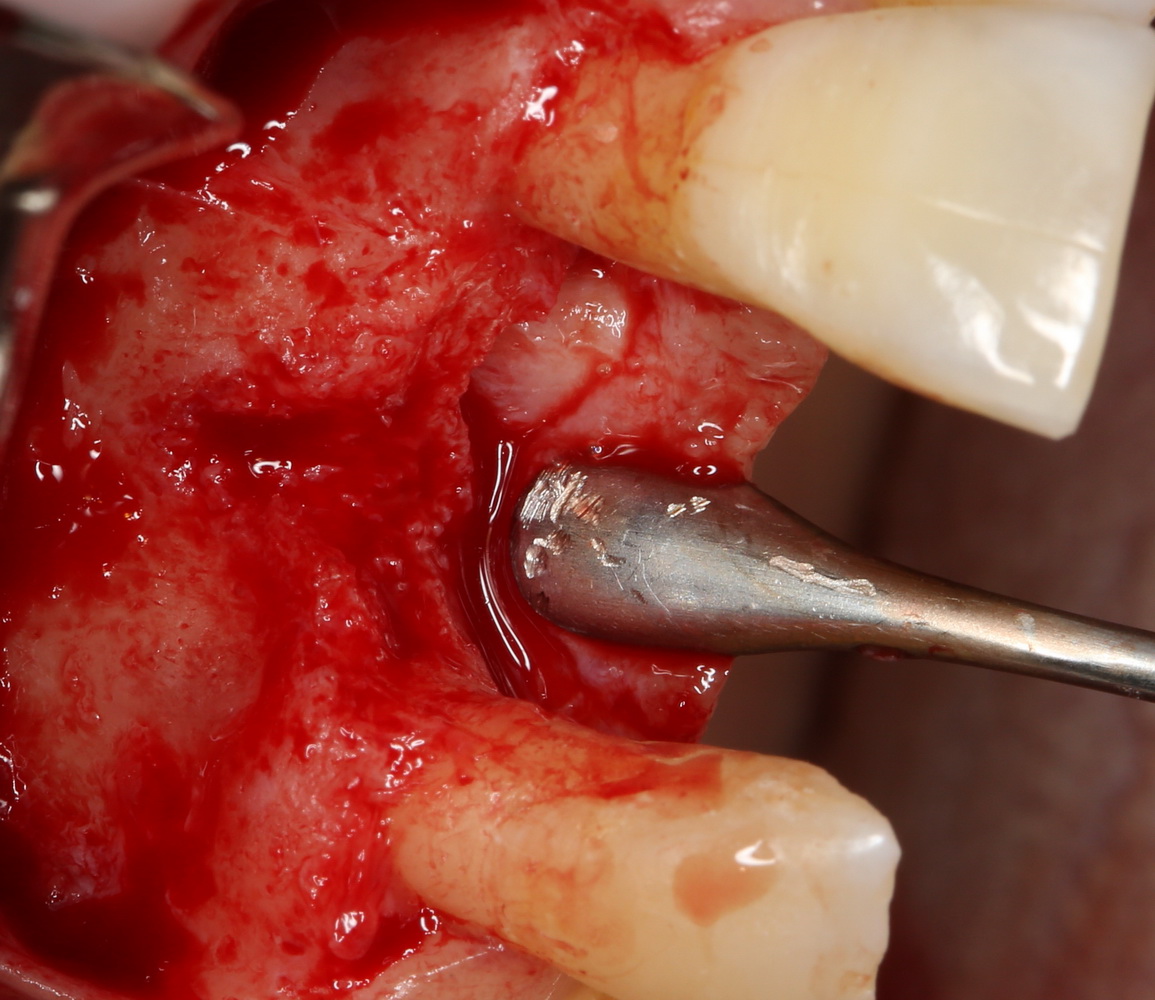

В отличие от костных блоков, делать забор аутокостной стружки можно в любом месте челюсти. Например, отдельным доступом через минимальный разрез:

или, непосредственно, со скелетированного участка операционной раны. Можно даже доступ для синуслифтинга сделать с помощью остеохарвестера, а заодно — собрать аутокостную стружку: